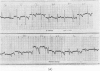

Three cases of the `Little Leopard' syndrome are described; its features are short stature, lentigines, electrocardiographic and ocular defects, pulmonary infundibular stenosis, abnormal genitalia, mental retardation, and deafness. The published material is reviewed, and the cardiac and electrocardiographic abnormalities are described in detail.